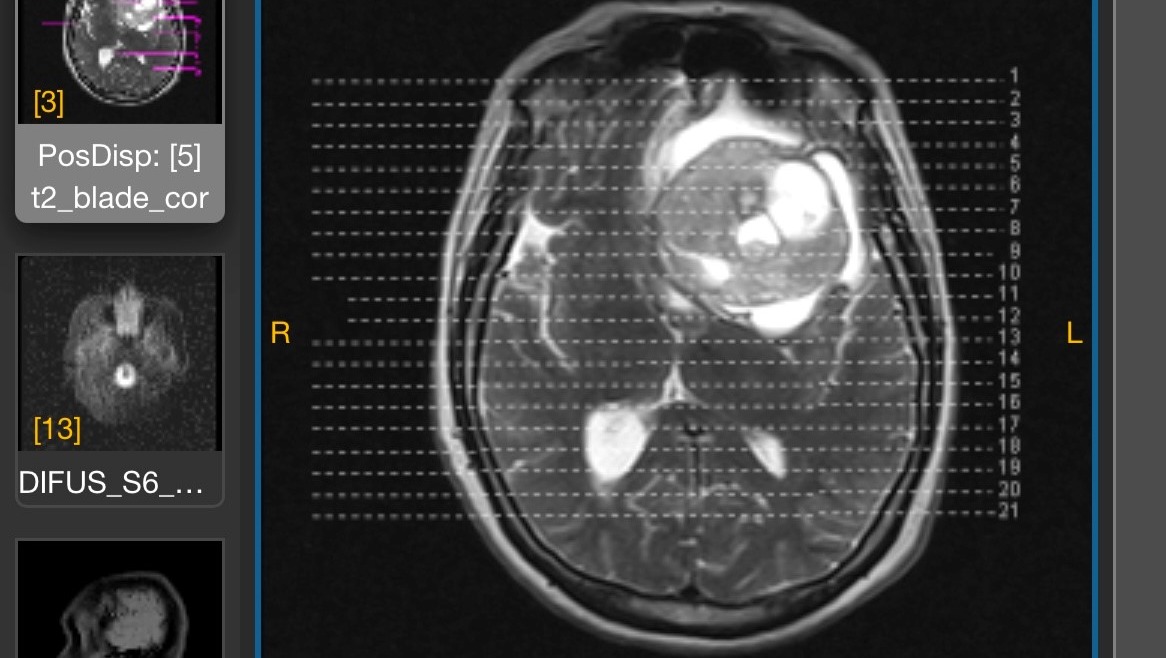

Edith Zambrano necesita someterse a una cirugía craneal de urgencia debido a un hallazgo en el area FRONTOPARIETAL diagnosticado como PROCESO MALFORMATIVO ANEURISMATICOS ARTERIOVENOSOS (TUMOR BENIGNO), lo cual actualmente esta causando pérdida de memoria, trastornos en el lenguaje, locomoción y control de esfínter , que conlleva a una intervención de urgencia para evitar daños progresivos, siendo vital para salvar su vida y garantizar su recuperación.

Edith Zambrano needs to undergo emergency cranial surgery due to a finding in the FRONTOPARIETAL area diagnosed as ARTERIOVENOUS ANEURYSMAL PROCESS (BENIGN TUMOR), which is currently causing memory loss, language disorders, locomotion and sphincter control, which leads to an emergency intervention to avoid progressive damage, being vital to save her life and guarantee her recovery.